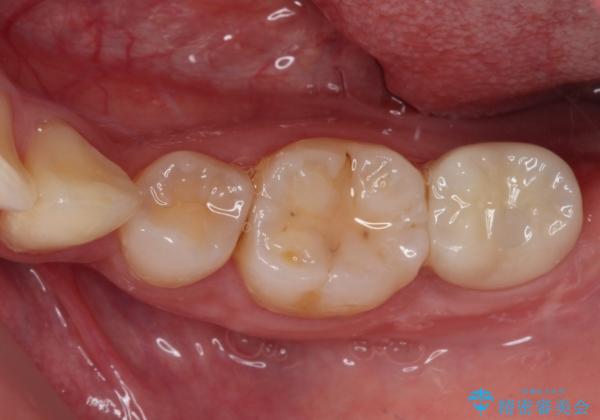

右下の歯は、レントゲン上歯髄組織まで虫歯が及んでいるように見えましたが、痛みの症状は強くなかったため、歯髄組織の一部を断ち歯根部分の組織を保存する生活歯髄療法を第一選択に処置を進めて行くこととしました。

まず生活歯髄療法を行い、その後部分矯正やインプラント処置を行いましたが、最初の処置から1年以上経っても右下奥の処置歯の神経組織に異常は認められませんでした。